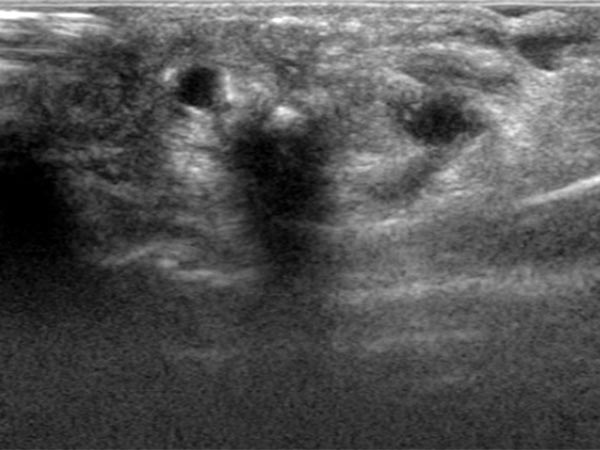

Ultrasound reveals a subcutaneous dilated drainage vein from the digital AVM at the third finger. Color-coded duplex ultrasound (CCDU) confirms the fast-flow arteriovenous shunt with high flow.

Percutaneous ultrasound-guided advancement of the puncture needle into the drainage vein of the digital AVM.

After embolization now clearly echogenic formations in the embolized vessel with dorsal acoustic shadowing due to the embolic agent after filling of the AVM nidus.